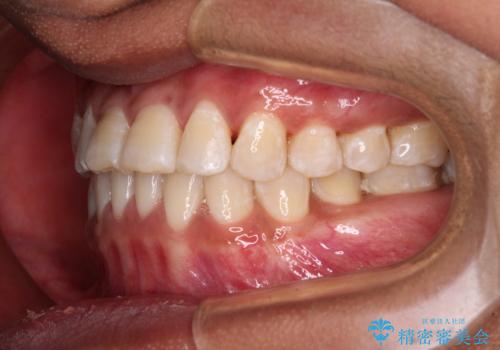

反対咬合の改善 途中で出産をしながらワイヤー矯正

- 前歯の隙間と反対咬合を気にして来院された患者様です。

咬合力が強く、反対咬合の改善に時間がかかりましたが、その後はスムーズに進めることができました。

途中、妊娠と出産があり、治療が中断したため、治療期間は延びましたが、出産も矯正治療も無事に終えることができました。